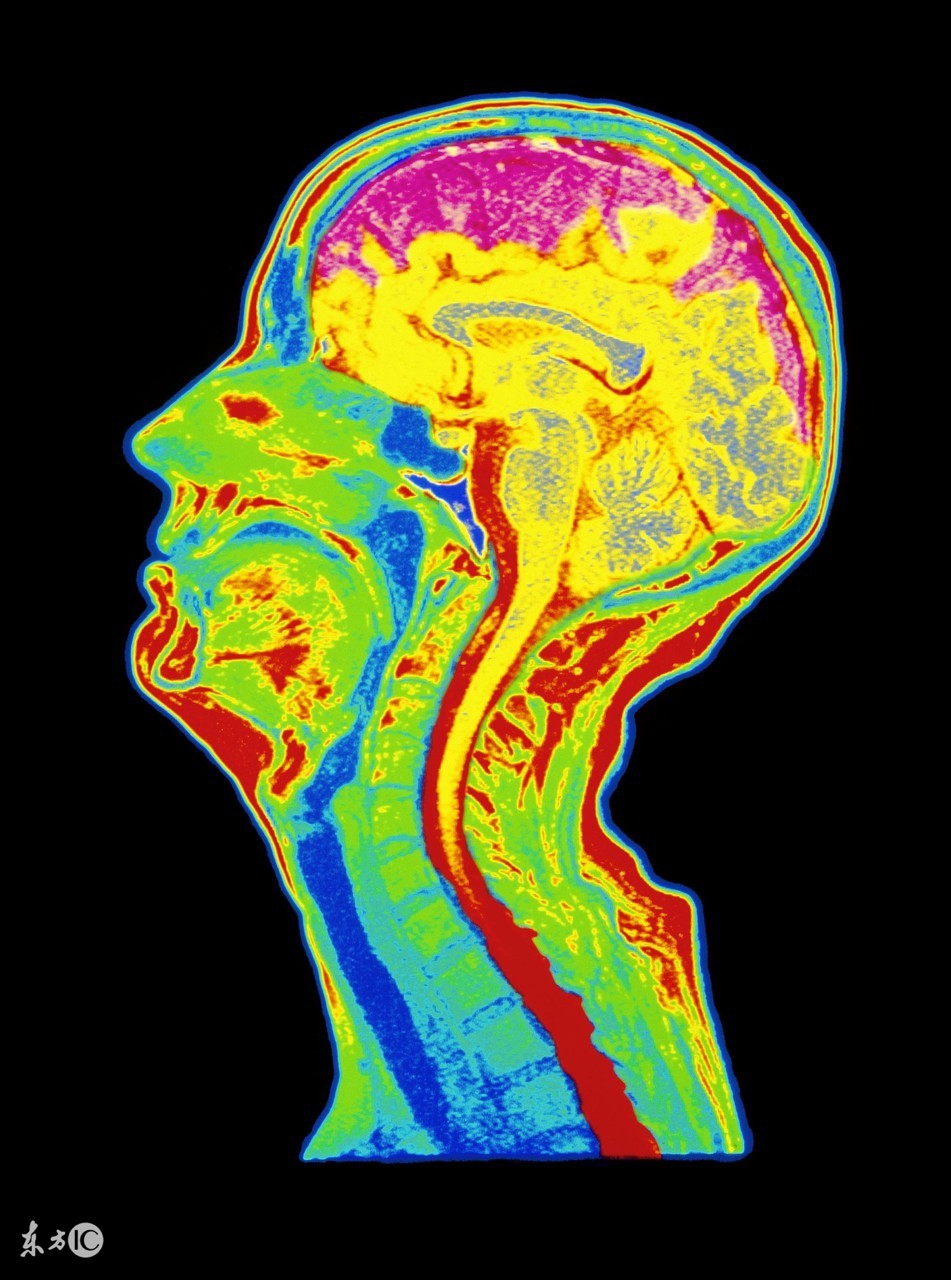

脑萎缩最主要的致病因素是脑血管长期慢性缺血,导致红细胞变形能力下降,微血管的有效血液灌注不足,脑组织处于慢性缺血、缺氧状态,脑细胞形态及功能受到影响,即形成脑萎缩。其病理变化可见脑回变平,脑沟增宽,脑室脑池扩大,脑重量减轻。多为大脑皮质萎缩。因萎缩部位和涉及范围不同又可分为局限性和弥漫性脑萎缩,大脑、小脑、橄榄体、桥脑萎缩,皮质型和中央型萎缩。

通过上面的知识普及,我们得到一句话,脑部供血不足是造成以上的问题,加强脑部供血是解决以上问题的根本方法,在我们目前常规方法执行的情况下,可以增加新的方法。脑部血管造影 发现血流减慢,血管阻力增加等现象,就像交通要道一样,容易堵的地方一般是颈部,可以在颈部加热,做颈椎操,促使血流加速,增加血流动力。或则选择颈椎全自动锻炼来解决自己没时间,没方法,不能坚持。具体颈椎操如图。